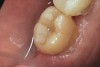

The next step was to re-prepare the enamel band on the outer perimeter of the tooth with either a carbide finishing bur or a diamond end-cutting bur (Figure 8). This removed any adhesive that inadvertently impregnated the enamel. At this point, the tooth was digitally scanned; if a two-appointment scenario had been utilized then the impression would have been taken and a provisional restoration placed.

The fit of the restoration was tried in and confirmed. The bonding surface of the ceramic restoration can be prepared by either using a conventional hydrofluoric acid conditioning followed by the application of a silane product, or an alternative method, which was used in this case, whereby phosphoric acid is applied to cleanse and hydrogenate the ceramic surface, followed by the application of a non-etching ceramic primer (Figure 9 and Figure 10). The tooth was then prepared by etching the entire prepared surface with phosphoric acid for 15 to 20 seconds then rinsed with water and dried (Figure 11). Only the enamel at this point was exposed to the phosphoric acid because the immediate dentin sealing step was previously completed. This selective etching step was accomplished without being concerned about etchant exposure on the dentin.

Figure 8  Re-preparing enamel with end-cutting diamond bur prior to digital scanning.

Figure 8

Figure 11  Enamel was etched with phosphoric acid prior to application of self-etching adhesive during cementation phase of the appointment.

Figure 11